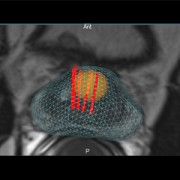

Utilisée dans le cadre de l’étude PRECISION, la plate-forme d’imagerie brevetée développée par KOELIS permet de visualiser, de localiser et de cibler précisément la tumeur au sein de la prostate. Son dispositif Trinity® agit comme un cartographe de la prostate affichant en temps réel et en 3D la prostate, les lésions suspectes détectées par l’IRM et l’emplacement des prélèvements réalisés par la biopsie ciblée. Les informations générées par l’examen du patient sont ensuite enregistrées dans un dossier personnalisé pouvant être superposé à l’image IRM à chaque examen pour suivre l’évolution de la pathologie.